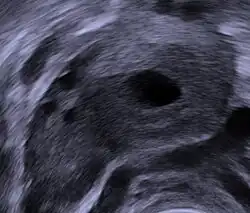

Human ovary with fully developed corpus luteum